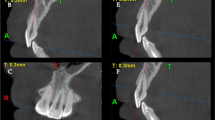

As a part of pre-treatment examination of each patient, CBCT (Finecube; Yoshida Dental MFG. Co., Tokyo, Japan) images of the maxillary and mandibular dentoalveolar regions were acquired for diagnosis and treatment planning, using the following settings: normal mode (16.8 s, 4.10 mGy, 90 kV, and 4 mA); slice thickness, 0.147 mm; field of view (FOV), 81 × 74 mm; and voxel size, 0.146 mm. All images were acquired with the head positioned along the Frankfort horizontal plane, running parallel to the floor. Images were saved as digital imaging and communication in medicine (DICOM) files, and sagittal and horizontal views of those were extracted and evaluated using an image analysis software (ImageJ version 1.48; National Institute of Mental Health, MD, USA). Prior to measurement, the three dimensions were calibrated and the three planes (i.e., sagittal, horizontal, and coronal) defined in each image (Fig. 1).

In the midsagittal plane, linear and angular measurements were defined as follows (Fig. 2):

Definitions of linear and angular measurements in the midsagittal plane. a PP palatal plane; L length of the incisive canal; θ1 and θ2 angles between the palatal plane and axes of the maxillary alveolar border and incisive canal, respectively. b θ3 angle between the palatal plane and axis of the maxillary left central incisor

P: palatal plane

L: length of the incisive canal

θ1, θ2, and θ3: angles between the palatal plane and axes of the maxillary alveolar border, the incisive canal, and maxillary left central incisor, respectively.

Linear and area measurements were acquired in the horizontal plane at three vertical levels: n, r, and o (levels of the nasal opening of the incisive canal, root apex of the maxillary incisor, and oral opening of the incisive canal, respectively; Fig. 3), and the distance from maxillary incisors to the incisive canal (D) and the cross-sectional area of the incisive canal (CSA) were measured at each level (Dn, Dr, and Do, respectively; CSAn, CSAr, and CSAo, respectively; Fig. 4). All measurements were performed by a single examiner, who repeated each measurement after a 2-month interval. The Dahlberg formula was used to calculate method error, as follows: